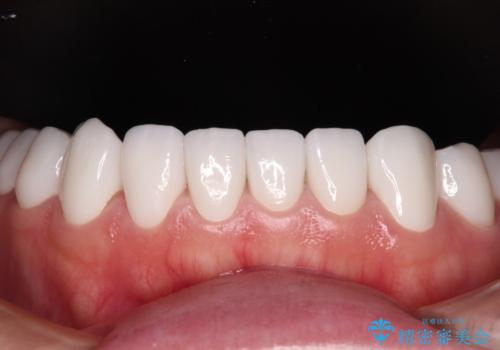

変色している歯をとにかく白く 全顎セラミック治療

当初は奥歯のみの治療をご希望でしたが、話を進めていくうちに、軽度ではあるものの、幼少期の薬の影響で歯が変色していることがコンプレックスであるということが分かりました。

長年歯の色が塞ぎ込んでいた部分があるとのことで、これを機会に全ての歯を真っ白にするために、オールセラミッククラウンにて補綴治療を行うこととしました。

より白さが目立つように、自然な仕上がりではなく、作り物の雰囲気があるフルジルコニアクラウンにて補綴治療を行いました。